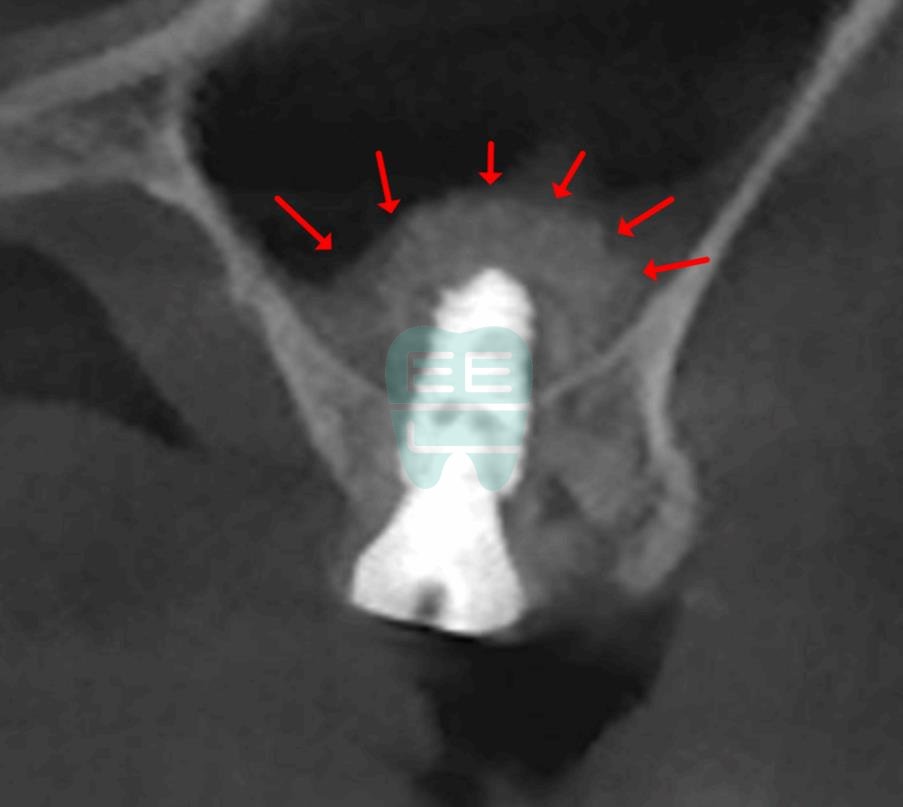

**Pre-operative CT Scan** — Insufficient bone height confirmed, sinus augmentation indicated.

**Post-operative CT Scan** — Maxillary sinus membrane safely elevated.